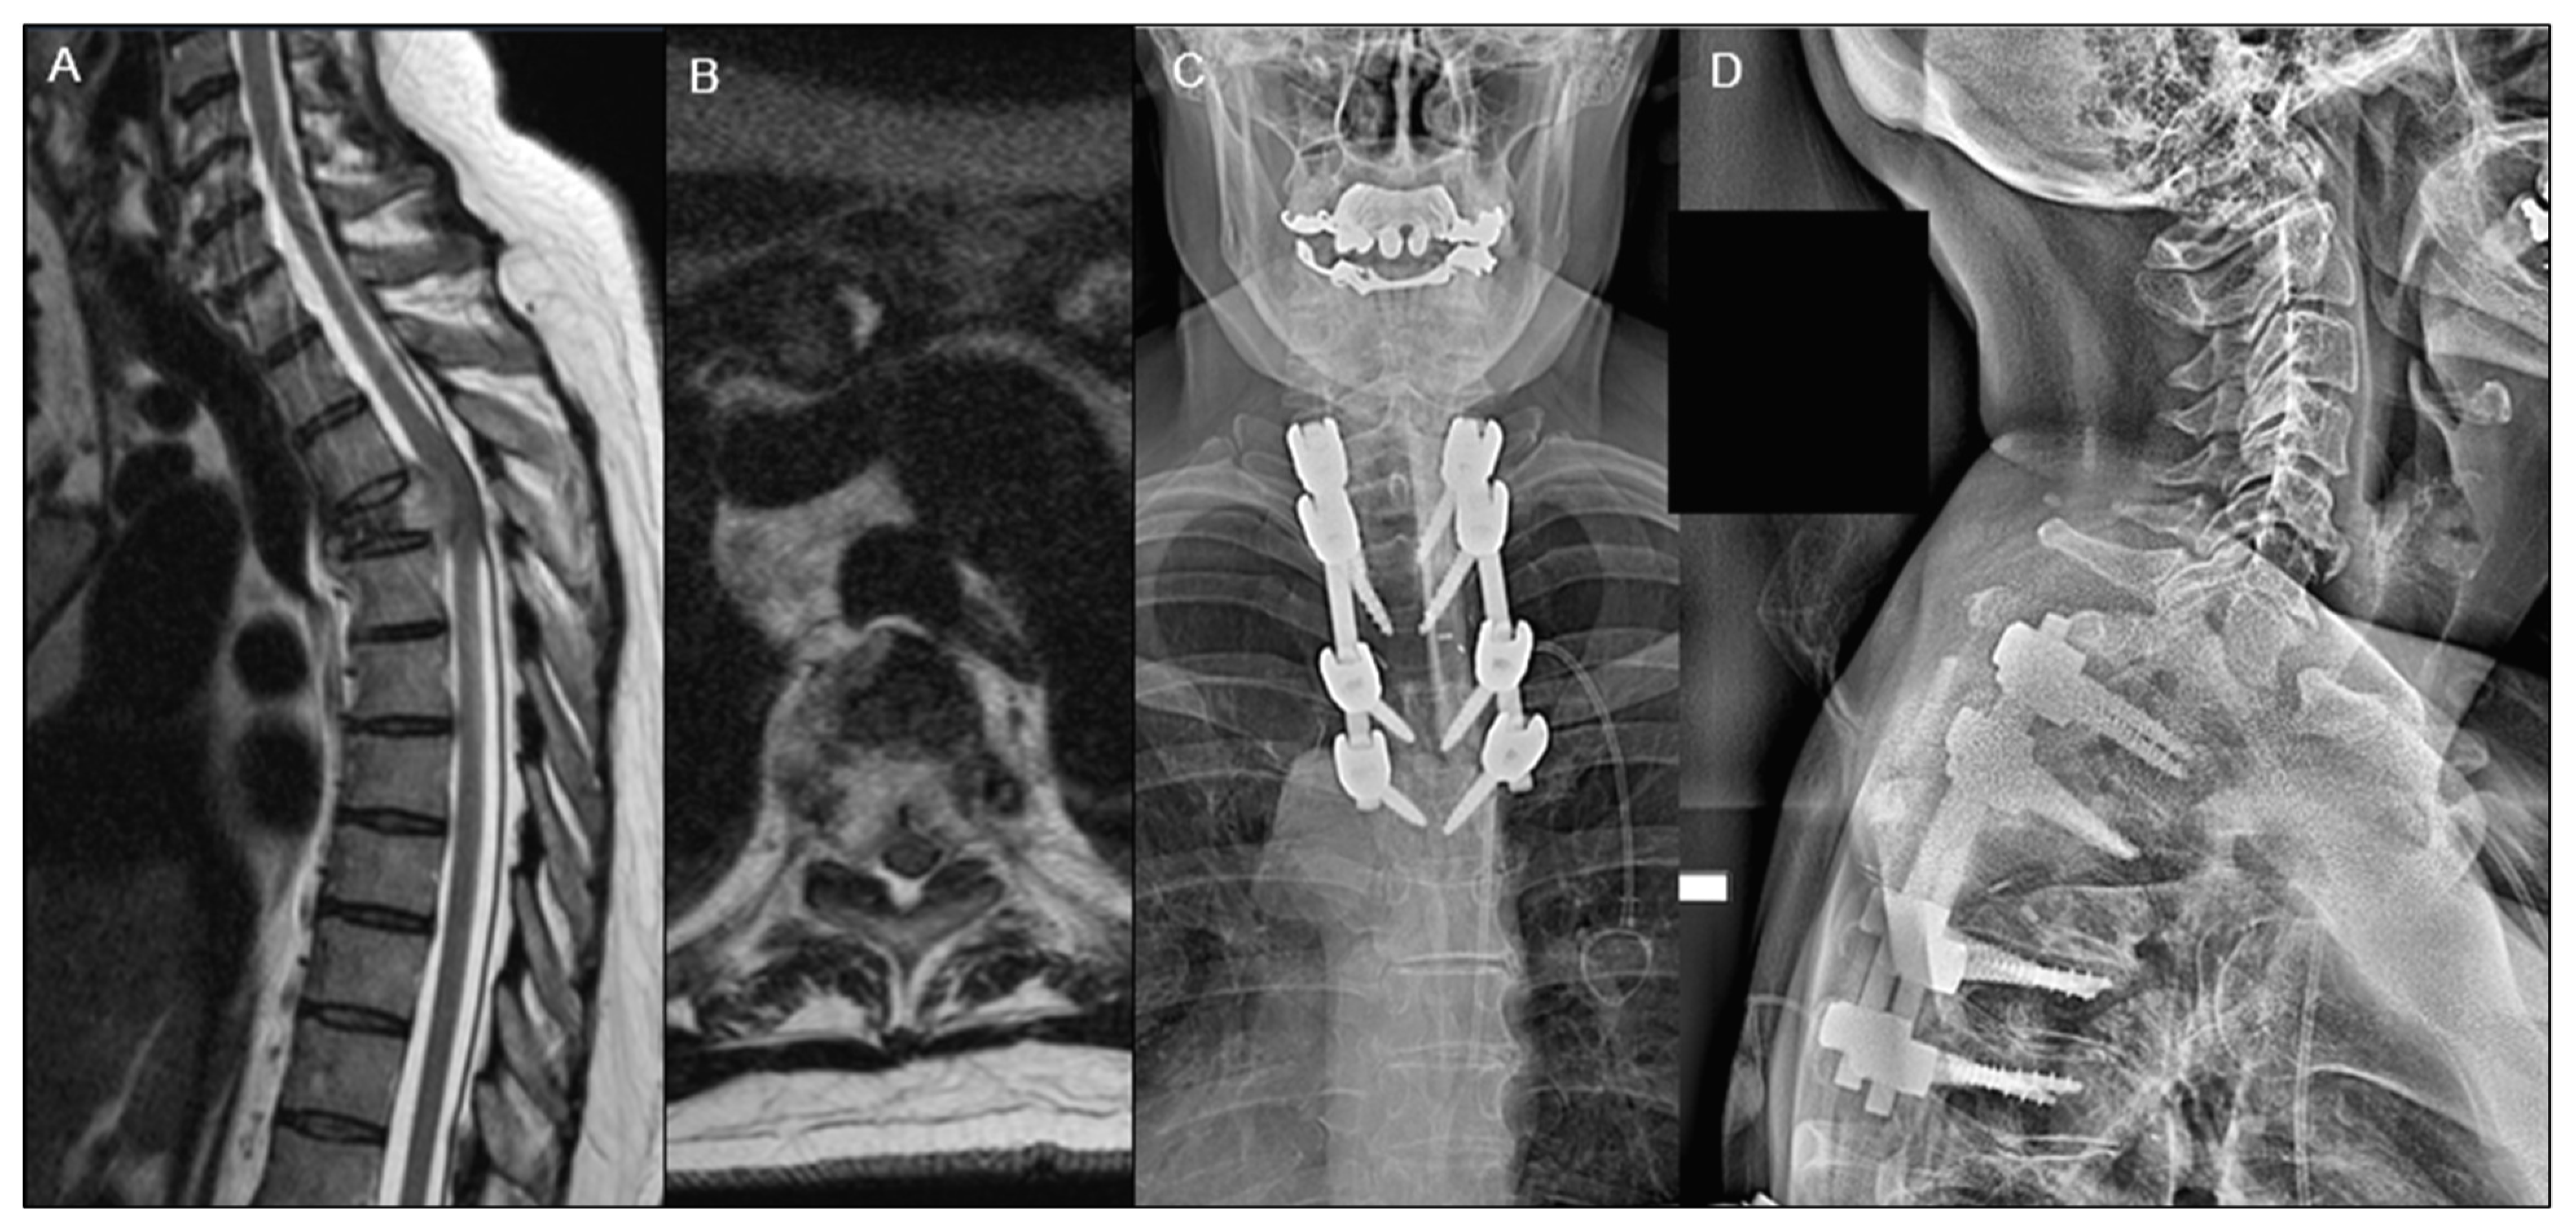

| Tumor Locations, n (%) | 0.351 | |||

| Cervical | 40 (12.9%) | 19 (11.8%) | 21 (14.0%) | |

| Cervico-Thoracic | 11 (3.5%) | 5 (3.1%) | 6 (4.0%) | |

| Thoraco-lumbar | 184 (59.2%) | 103 (64.0%) | 81 (54.0%) | |

| Lumbar | 76 (24.4%) | 34 (21.1%) | 42 (28.0%) | |